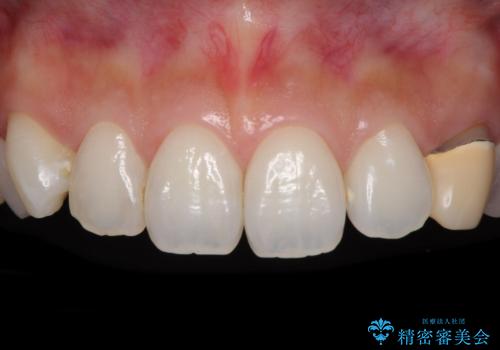

[前歯の変色] 前歯の見た目を改善したい

![[前歯の変色] 前歯の見た目を改善したいの症例 治療前](https://seimitsushinbi.jp/wp/wp-content/uploads/2021/05/510b0093313ff75fbcb626419a0f3045-500x350.jpg?v=1622180184)